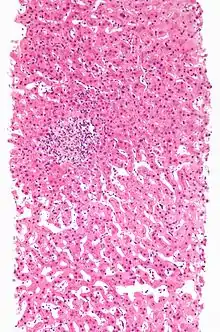

| A rash due to a drug reaction |